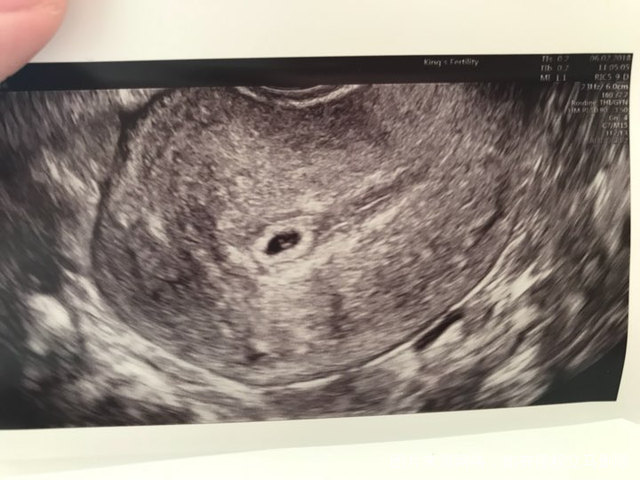

移植第二十天阴部B超

前期hcg翻倍不太好,大概才60%,加上前两天擦拭有褐色渣状物,便央求医生帮我提前看看。

因为是加插的,而且时间还较早,医生说只能告诉我宫内孕,可以看见卵黄囊,但不准备仔细往下看了,让我等到七周再来做一超。我再三询问能否看到出血点,医生又快速瞟了一眼说没有,她估计可能是宫颈引起的出血。说完就赶我出来了。[微笑]

有懂看B超图的姐妹帮我看看还能看到什么信息吗?谢谢![鼓掌][鼓掌][鼓掌]